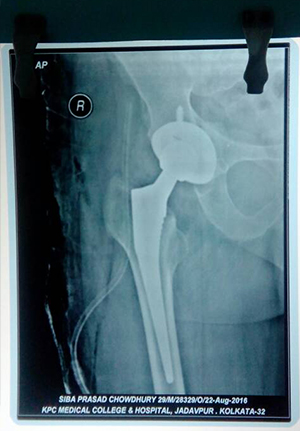

primary total hip replacement in ankylosing hip

Proximal femoral nail for comminuated subtrochanteric fracture

Complex primary total hip replacment after failed internal fixation